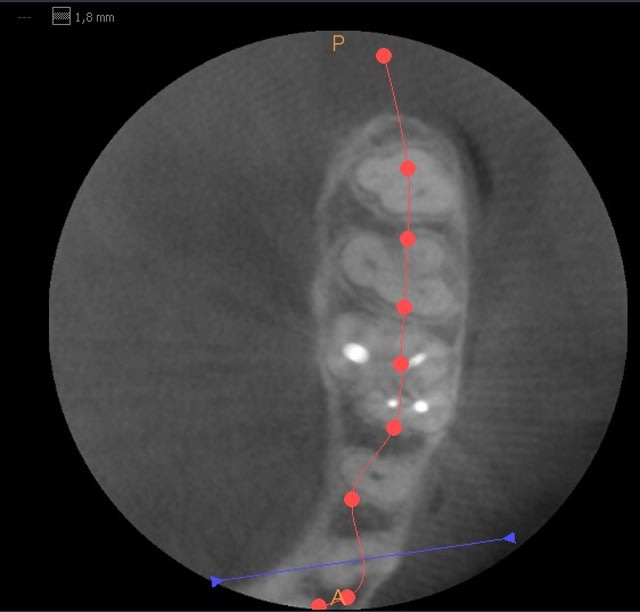

Faudrait que je vous fasse quelques copies d'écran mais dores et déjà je trouve que les clichés sont vraiment de bonne qualité. Quel confort! les mesures se font au quart de poil.

les premières copies d'écran (je ne maîtrise pas encore le logiciel)